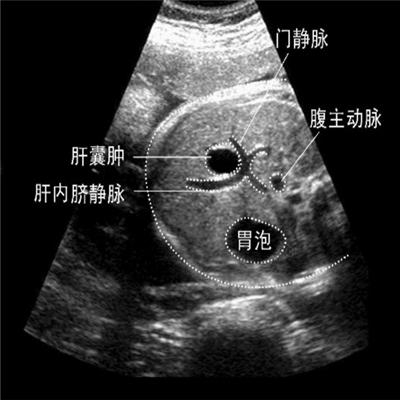

1 其一:若是在生活中得上了肝囊肿这个疾病的话,要知道肝囊肿属于一种良性的病变,因此对于小的肝囊肿患者可以不用担心,但是要定期的到医院进行检查,防止出现囊肿的增大,一般来说肝囊肿的增长是非常缓慢的。

2 其二:若是在生活中得上了肝囊肿这个疾病的话,若是单纯性的肝囊肿,如果体积比较小的时候可以不用进行手术的疗法,主要注意自己的观察。

3 其三:若是比较大的肝囊肿,可以采用手术治疗的方法手术切除,这是是一个非常有效的治疗方法。一般来说,肝囊肿是不会发生恶变的,但是如果患者是由于一些阻塞、或者是炎症导致的肝囊肿,一定要注意进行治疗。